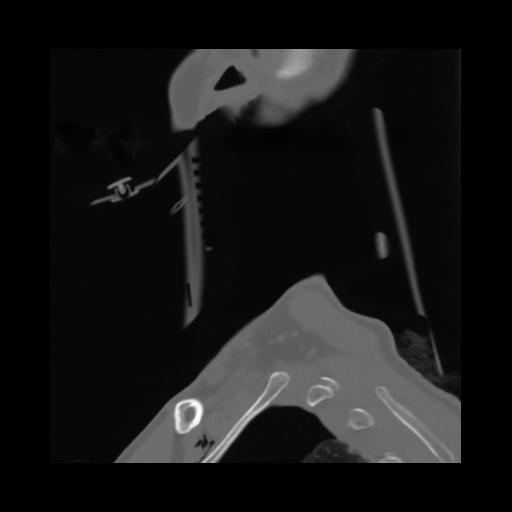

14 P.BLANDAS,,Sagittal,2.000,P.BLANDAS,Sagittal,